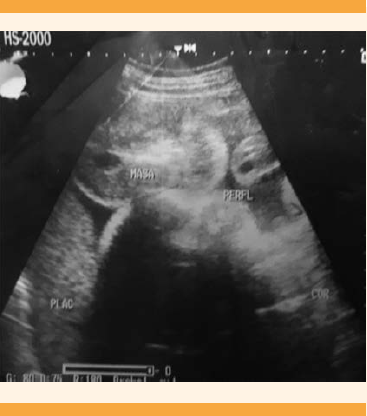

Paciente de 16 años, primigesta, sin antecedentes personales patológicos ni quirúrgicos referidos. El control prenatal se inició a las 15 semanas de embarazo por fecha de la última menstruación. El único ultrasonido obstétrico (Figura 1) reportó embarazo con un feto de 27.2 semanas de gestación, con presentación pélvico, peso 1051 g, índice Phelan 12.3 cm, placenta corporal posterior grado I, normoinserta, con observación de una gran masa compleja, adosada a la placenta, de aproximadamente 9.2 x 7.1 cm de probable apariencia trofoblástica de causa indeterminada. Ingresó a la sala de tococirugía con trabajo de parto y feto en presentación pélvica. Se obtuvo por cesárea, sin complicaciones, una niña con APGAR 8-9, de 2800 g, talla de 49 cm, 40 semanas de gestación por Capurro. El gemelo estaba malformado y midió 15 x 13 cm, constituido por una masa ovoide, amorfa, cubierta de piel, sin genitales externos definidos, polo cefálico con pilosidad fina, sin facciones reconocibles, tronco o extremidades, excepto una prominencia inespecífica que simulaba una probóscide. En el tercio medio de la cara anterior se encontró el cordón umbilical implantado de 12 cm de longitud (Figuras 2 y 3). Al corte se observó una vena dilatada y una arteria única e hipoplásica, la cara posterior lisa, solo con pilosidad fina. El gemelo superviviente fue dado de alta del hospital junto con la madre, sin complicaciones aparentes.

Figura 1 Caso 1: Ultrasonido pélvico de embarazo gemelar monocorial monoamniótico con un feto normal y el otro acárdico. Reporte: gran masa compleja adosada a la placenta.